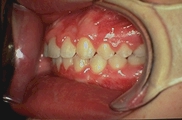

Chez l’enfant Chez l’adulte

Les dents supérieures trop " en avant ". Les dents se chevauchent.

ROLES ESTHETIQUE ET FONCTIONNEL

Toutes les dents sont alignées. L'esthétique et l'efficacité masticatoire sont optimisés.